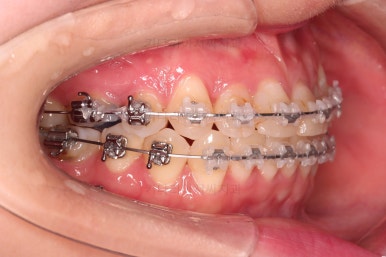

옆모습 중간중간 체크해 주고요.

이번 환자분은 옆라인이 애초에 매우 좋으셨기 때문에 입매를 바꾸지 않아야해서 오히려 더 세심한 치료가 필요한 환자분이셨습니다.

공간을 줄여나가고 순차적으로 충치치료도 마무리 해갑니다.

교합이라던가 부족한 부분을 좀 더 마무리하고요.